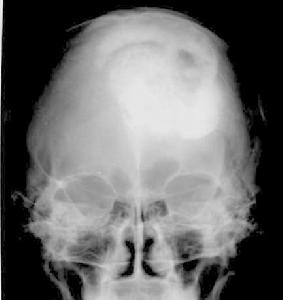

CT圖在CT出現以前,根據病人的臨床表現,再輔以頭顱平片和腦血管造影,對腦膜瘤即可作出確診。CT的出現,使眶腦膜瘤的定位以及定性診斷水平大大提高,典型的眶腦膜瘤,在未增強的CT掃描中,呈現孤立的等密度或高密度占位病變,其密度均勻一致,邊緣清晰瘤內可見鈣化。